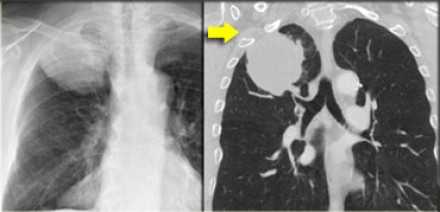

Рак Панкоста

Типичные проявления рака Панкоста следующие:

- боли, обусловленные инвазией в плечеголовное сплетение.

- синдром Горнера

- деструкция костных структур

Выполнение МРТ приоритетнее в связи с лучшим мягкотканным контрастом в сравнении с КТ.

На Т1-изображениях представлен пациент с раком Панкоста Т3-стадии в связи с тем, что поражены корешки только Th1, Th2

- ПкА = подключичная артерия,

- ПЛМ = передняя лестничная мышца.

(Courtesy of Wouter van Es, MD. St. Antonius Hospital Nieuwegein, The Netherlands)